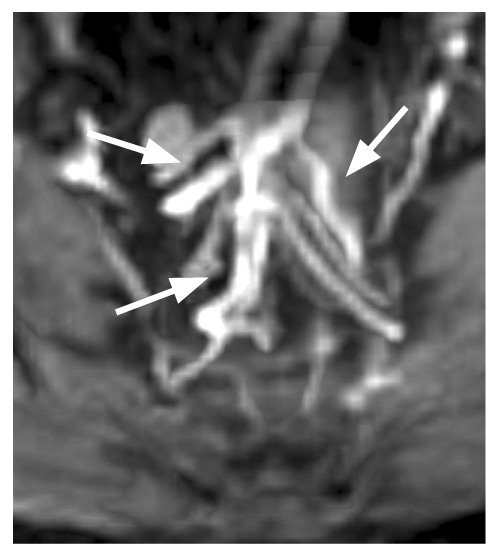

Fig. 4. Three branches of the superior rectal artery at the site of origin (arrows). Classical (type 1) anatomy of the superior rectal artery.

Fig. 5. Three branches of the superior rectal artery before the bifurcation (arrows). Classical (type 1) anatomy of the superior rectal artery.